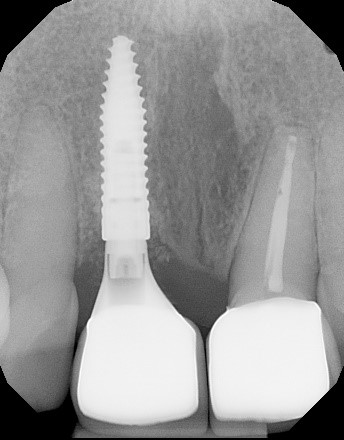

21/22 - Radiographs during therapy.Immediate implant placement and regeneration of ridge using an allograft bone ring and Jason® membrane - Drs. Miller and Korn

22/22 - Final radiograph one week post insertion.Immediate implant placement and regeneration of ridge using an allograft bone ring and Jason® membrane - Drs. Miller and Korn